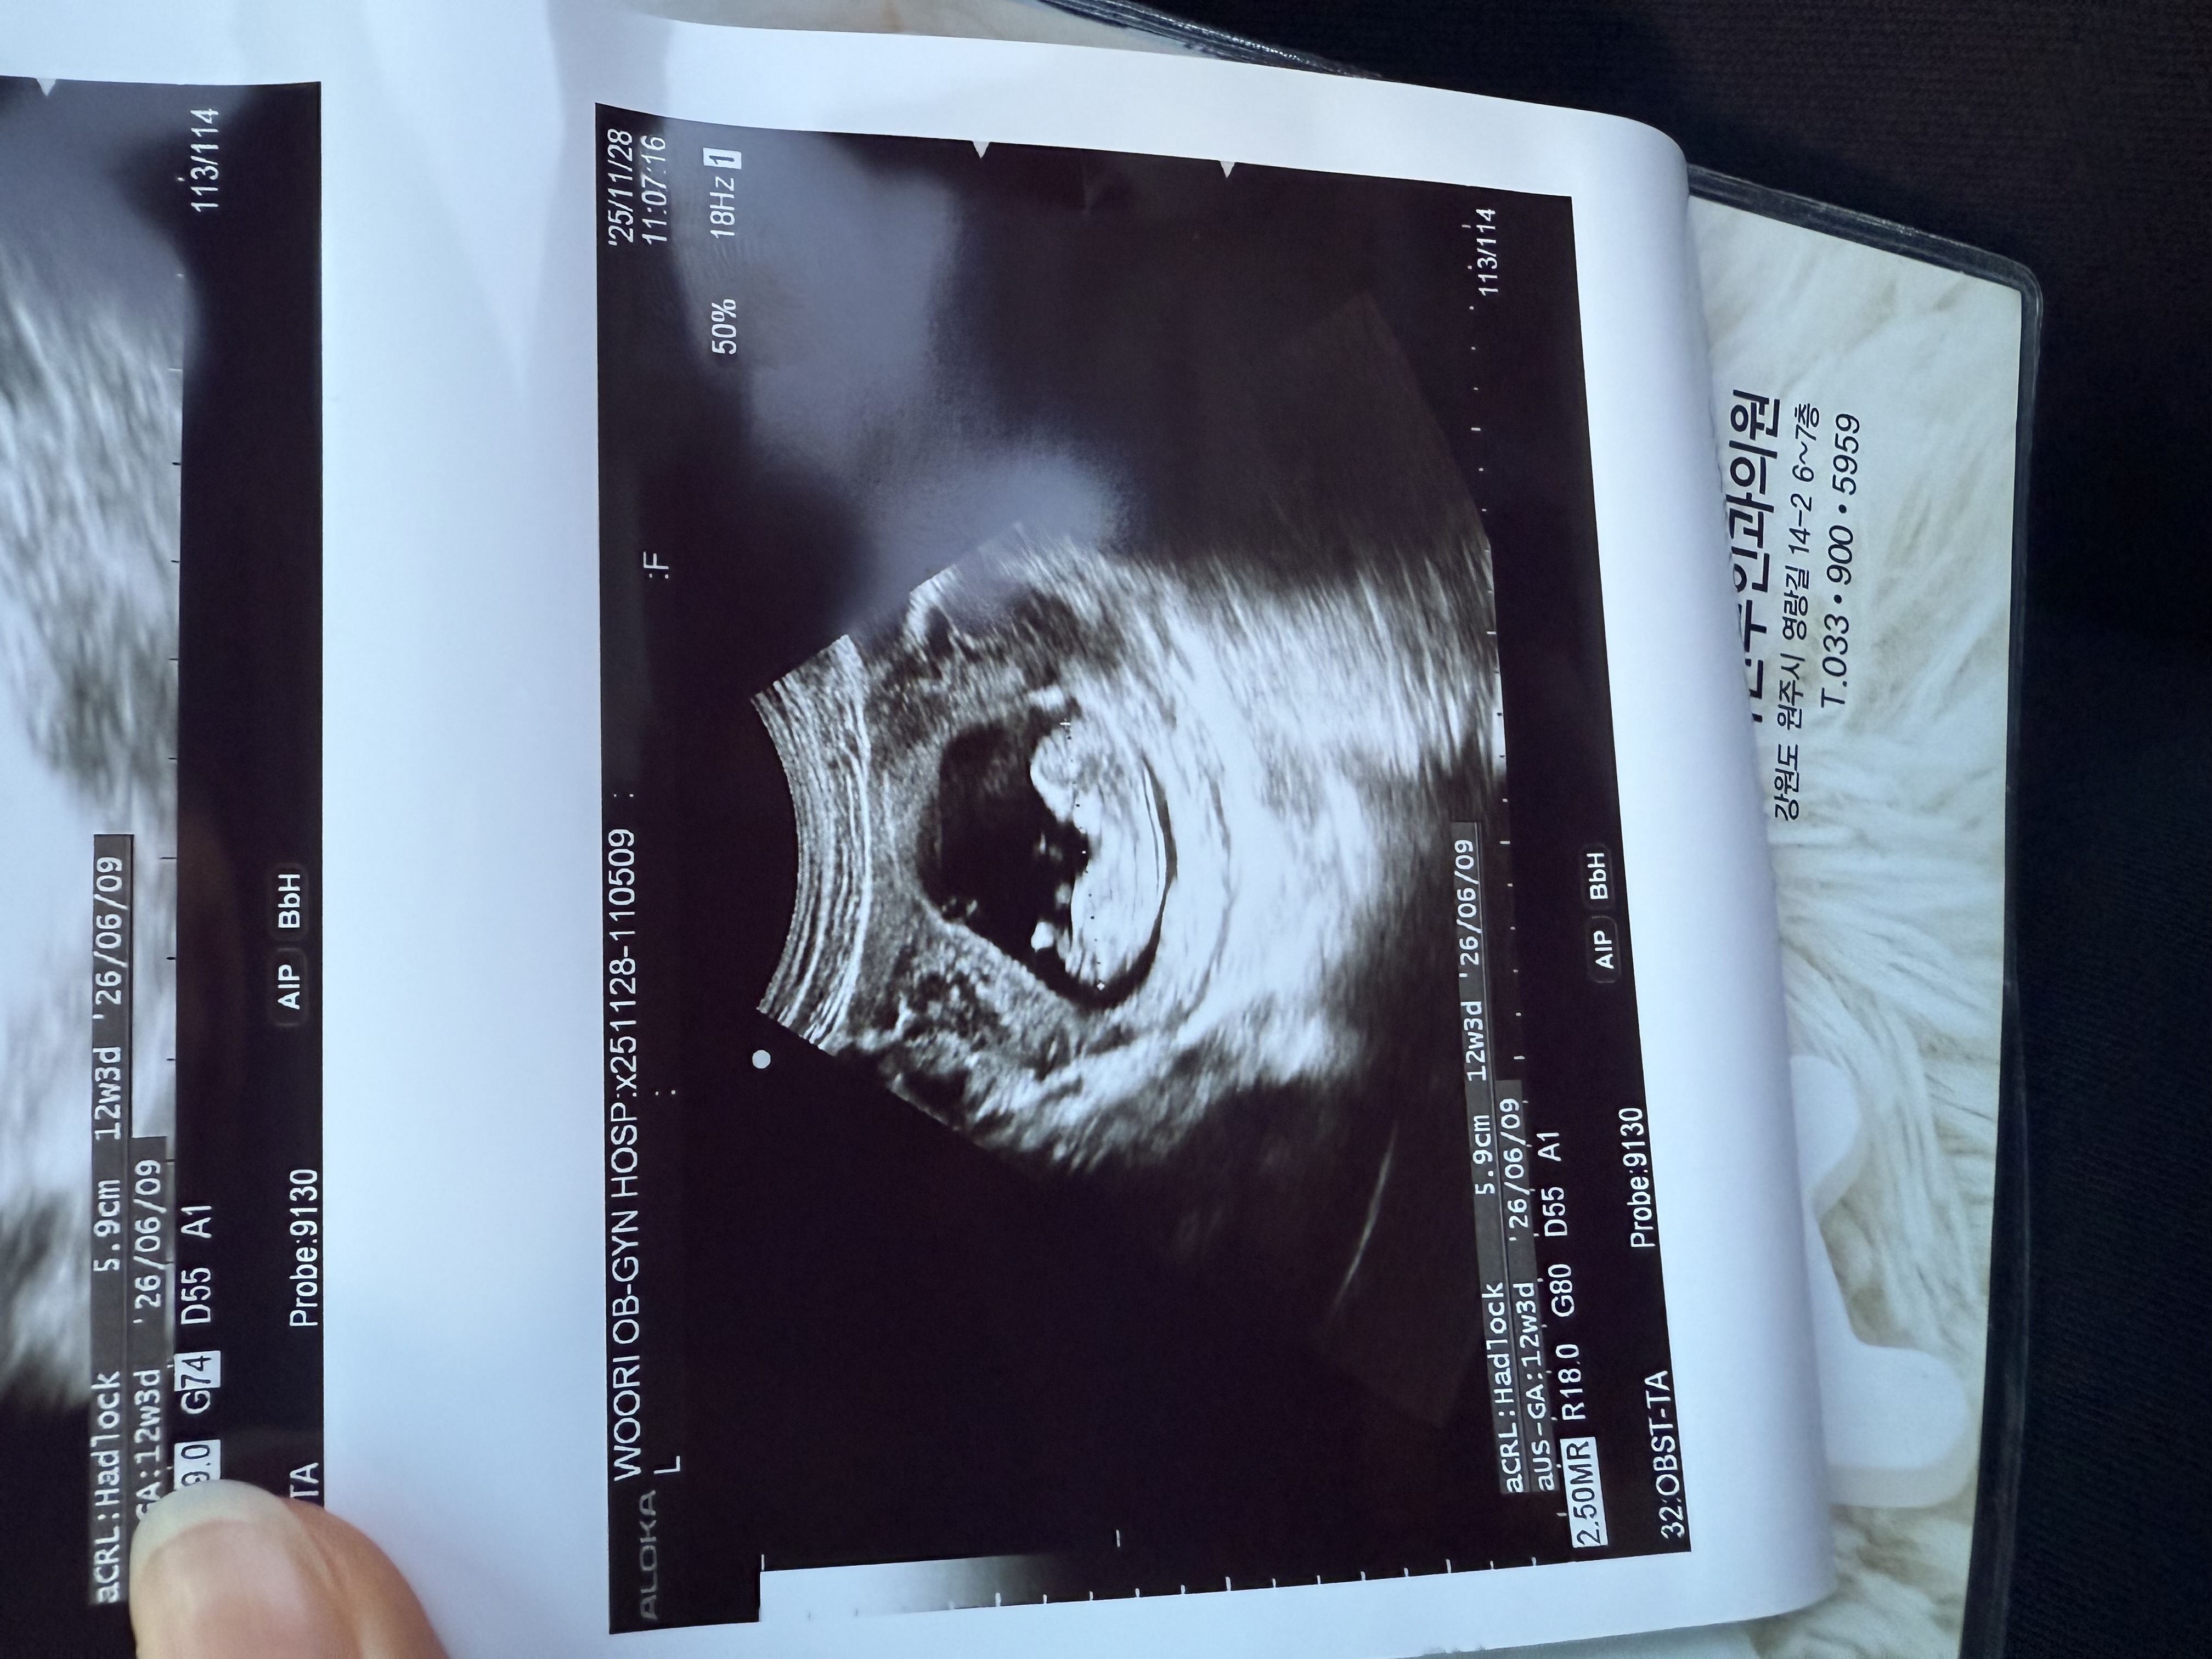

여자일까요 남자일까요 ㅠ

궁금하네요 ㅠㅠ

여아같아요..!!